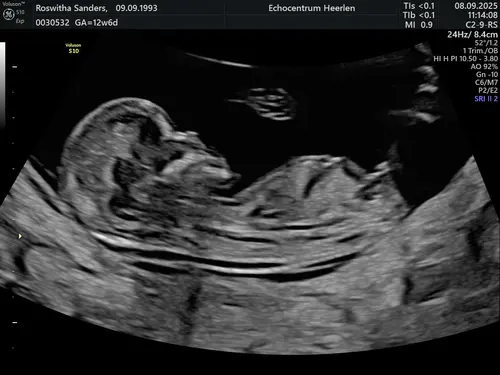

Ik zelf zie hem ook niet echt maar ook te weinig verstand van ik zal nog eens een andere erbij zetten van dezelfde echo

Oeh lastig, ik zie wel een nub maar vind het lastig om te zien of deze nu meer in een driehoek staat tov de ruggengraat of dat het recht door loopt 😅. Misschien zijn er kenners die het zien?